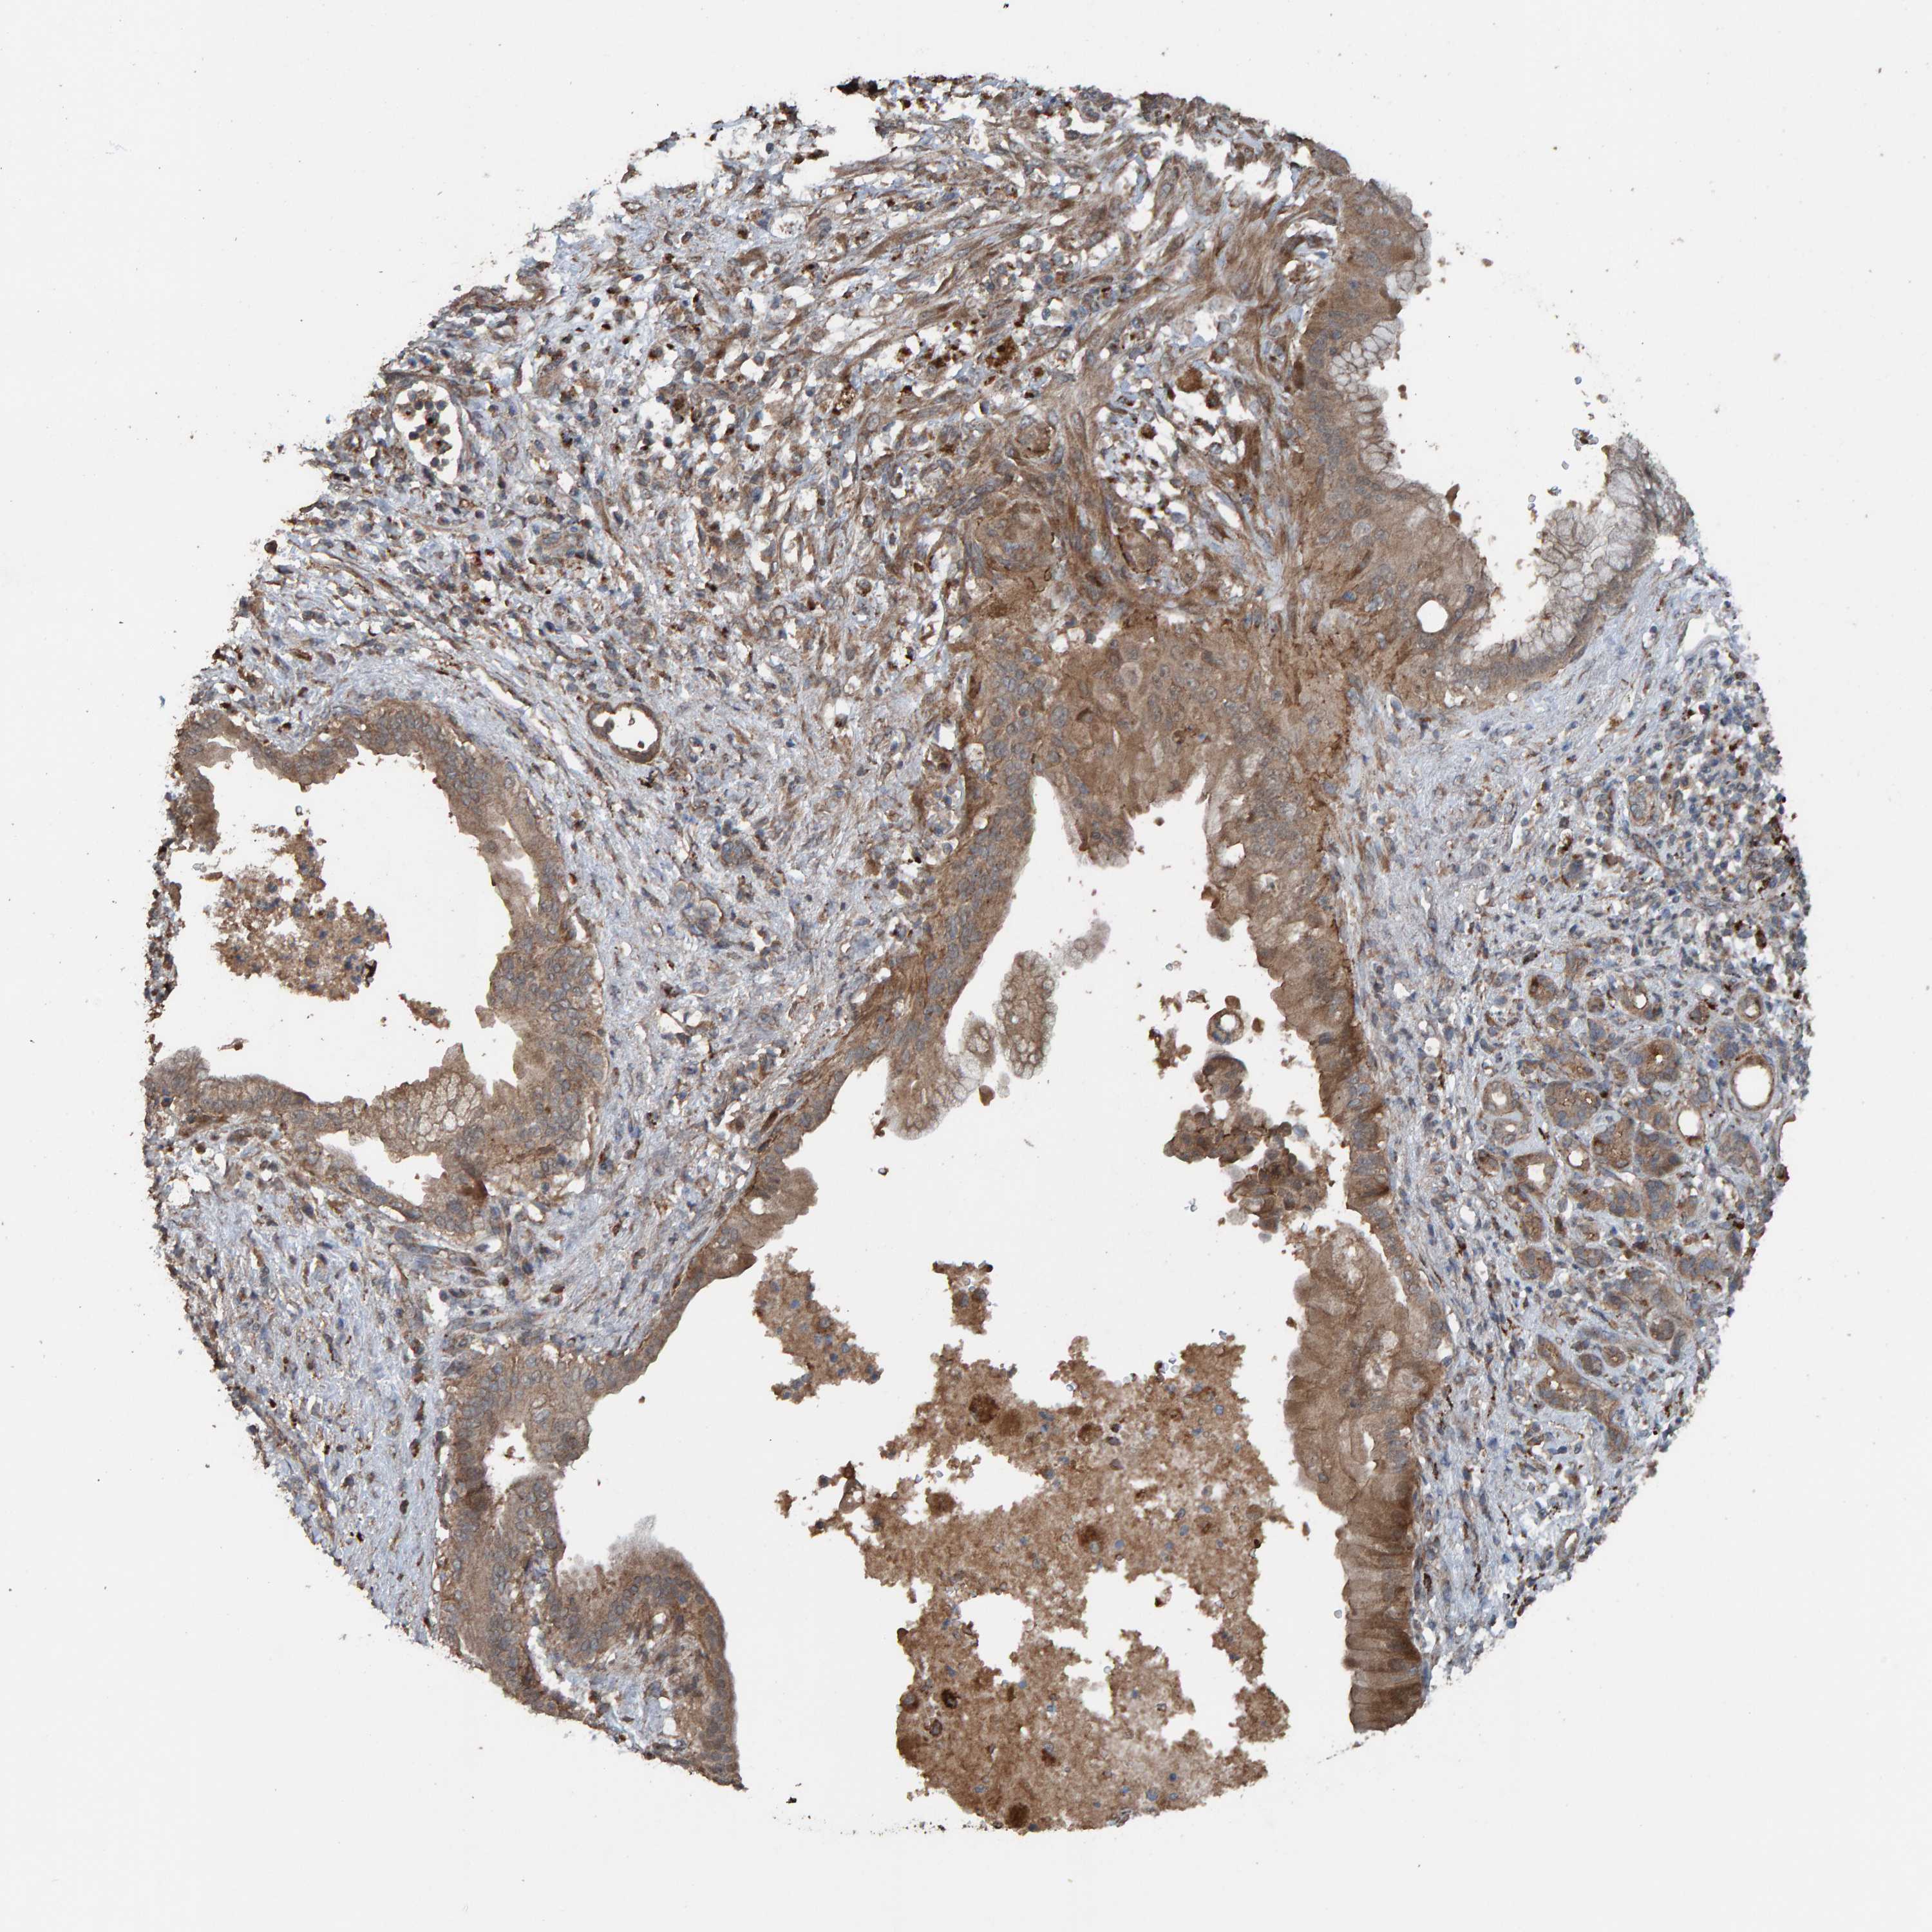

PANCREATIC CANCER - Protein expressioni

A mouse-over function shows sample information and annotation data. Click on an image to view it in a full screen mode. Samples can be filtered based on level of antibody staining by selecting one or several of the following categories: high, medium, low and not detected. The assay and annotation is described here.

Note that samples used for immunohistochemistry by the Human Protein Atlas do not correspond to samples in the TCGA dataset.

Antibody stainingi

Antibody staining in the annotated cell types in the current human tissue is reported as not detected, low, medium, or high, based on conventional immunohistochemistry profiling in selected tissues. This score is based on the combination of the staining intensity and fraction of stained cells.

Each image is clickable and will lead to virtual microscopy that enables deeper exploration of all samples and also displays staining intensity scores, fraction scores and subcellular localization as well as patient and tissue information for each sample.

Antibody HPA023384

Staining

High

Medium

Low

Not detected

Intensity

Strong

Moderate

Weak

Negative

Quantity

>75%

75%-25%

<25%

None

Location

Nuclear

Cytoplasmic/membranous

Cytoplasmic/membranous,nuclear

Adenocarcinoma, NOS